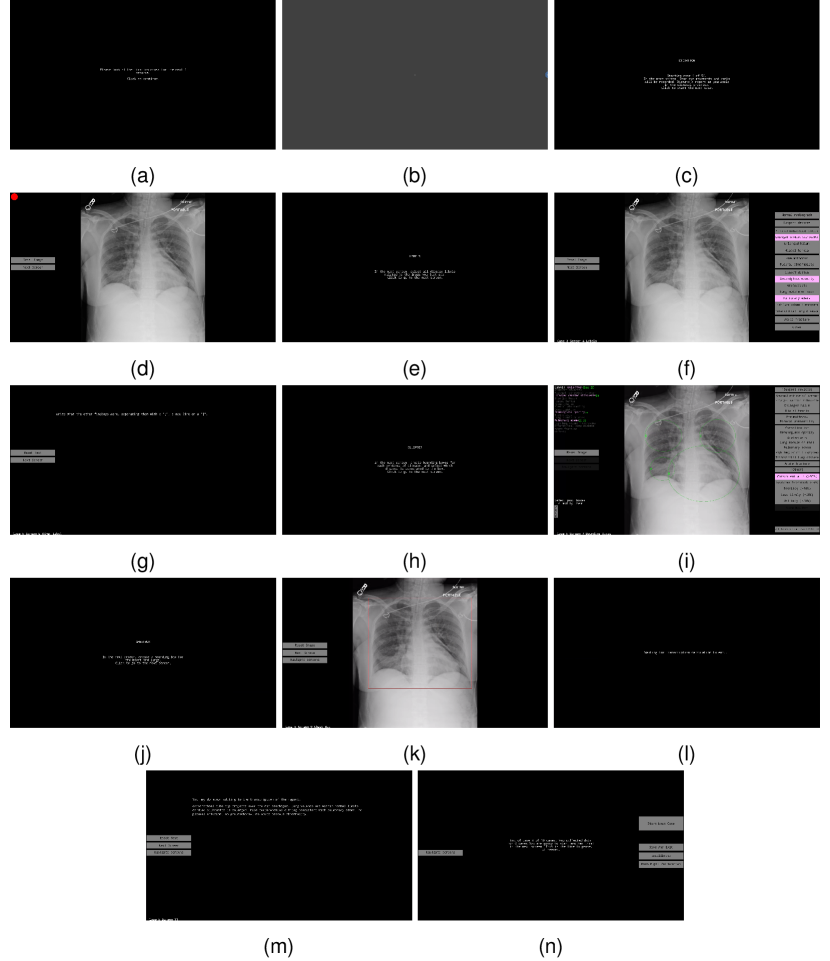

Data collection for each CXR involved two main parts: a dictation and transcription of a free-form radiology report while collecting eye-tracking data, and the selection of labels and ellipses to use as evaluation ground-truth for anomalies present in a CXR and their location. The data collection interface was developed in MATLAB R2019a/Psychtoolbox 3.0.17 [25, 26, 27]. The code for the interface is available at https://github.com/ricbl/eyetracking [28]. The interface is shown in Figure 2 and as a video in Supplementary File 2, where the moving semitransparent red ellipse, with an axis length of 1° of visual angle, represents stabilized gaze, i.e., fixations, and the moving blue ellipse represents the instantaneous gaze location sample. The cursor was not drawn in the video and the audio is a digitally generated voice representing the timestamped transcription. We did not include the original dictation in the video for anonymization purposes. This interface allowed for:

Figure 2: Screens of the data-collection interface in the sequence they are presented to a radiologist, including instruction screens (a, c, e, h, j, n), calibration of pupil size (b), dictation of reports (d), choice of global labels (f, g), selection of ellipses and certainties (i), drawing of lung/heart box (k), and editing of transcription (l, m). Digital visualization is recommended for reading the content.